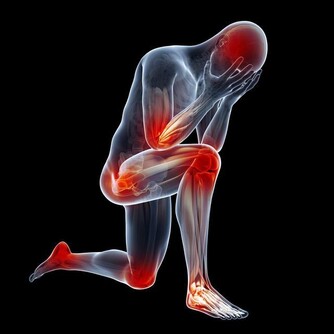

一旦患病,不但會使患者出現一些排尿異常現象,還會使患者的腰腹部、會陰、恥骨等部位出現疼痛感,並且會影響到患者的性功能。

大部分人認為,男性受寒並不會影響到身體健康,這種說法是錯誤的。如果男性的腹部和腰部受到寒涼之氣的侵襲,就會影響到整個骨盆區域的血液循環,從而導致前列腺部位血流不暢。

還會導致前列腺和整個盆腔部位的肌肉異常痙攣,患上前列腺炎以及其他男性生殖疾病的概率會特別高。